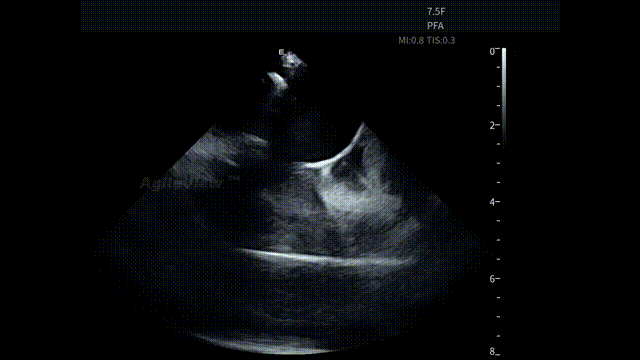

手术开始后,蒋晨阳教授将 AgileView™ 7.5Fr ICE 导管置入右心房,首先通过 HomeView 视角建立心腔整体参照,并对左心耳血栓及心包情况进行系统性评估。术前影像显示心包存在少量积液,为后续操作提供了重要的基线参考。

HomeView

左心耳血栓筛查

术前心包筛查-有少量积液

术后心包筛查-积液无变化

术中,基于AgileView™ ICE 7.5F的产品优势,蒋晨阳主任团队将ICE导管打A弯跨三尖瓣进右室,松弯卡室上嵴,顺转后打到左房长轴切面,以便更好地进行导管封堵/贴靠与位置的判断,在AgileView™ ICE实时影像的指导下,PulseSelect™ 脉冲消融导管安全进入左心房,先后完成双侧肺静脉隔离及MTI、roofline、后壁BOX、SVC隔离, ICE下可见导管贴靠良好,整个消融过程顺利,消融时间约50分钟。术后患者恢复良好。